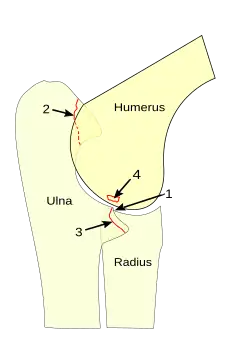

Panner Disease affects the elbow of the arm. At the elbow, the humerus meets the ulna and the radius. The humerus is the long bone that runs from the shoulder to the elbow, and the ulna and radius are the two bones that make up the forearm.[6] The capitellum is the rounded knob on the end of the humerus and it is held by the radius due to the radius's cup-like shape. Panner Disease is part of a family of bone development diseases known as osteochondrosis.[6][7] In osteochondrosis, the blood supply to an area of developing bone in the dominant elbow is temporarily disrupted by something that is not yet well understood.[6] Therefore, the tissues in the bone are not getting enough blood and they begin to go through necrosis, and they begin to die. Normally, bones grow by the expansion and uniting of the growth plates, but osteochondrosis disrupts this process and the result is cell death and the loss of newly formed tissue. The death of the tissues eventually leads to deterioration of the bone's growth plate. The bone's growth plate is defined as the area at the end of a developing bone where cartilage cells change into bone cells.[6] The bone tissue does regrow, but the necrosis can cause temporary problems in the affected area until the strenuous arm and elbow activity is significantly decreased or stopped for a period of time.[6]